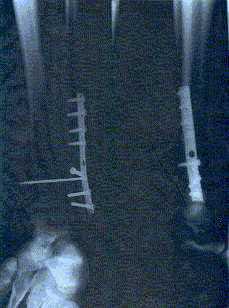

In terms of broken bones from unicycling accidents, I know of 3 broken ankles and 2 broken wrists. I think it is between Ken and Dustin as to who has had the worst accident while unicycling. Both managed to totally snap through bones, requiring much addition of metal to their legs.

I think Dustin wins hand down (or legs down). If I remember rightly, he broke both his Tibia and Fibula which required a lot of hardware to stabilise. I broke my fibula and tore my deltoid ligament, although it was quite a bad and unstable Webber Type C fracture.

Unicycling is an extremely dangerous sport. In 10yrs of MTBking I’ve had nothing more than a few scratches and 7 stitches. in 8yrs of TaeKwondo I’ve had nothing more than a few whacks in the head and some bruises. In less than two years of unicycling I’ve had 12 stitches, about 4 badly sprained ankles (two were hyperdorsiflexion injuries while doing drops, the others were sticking my foot in awkward places on UPD’s.), three sprained fingers, numerous scars all over my shins and back of my calf from my pedals, one Weber C ankle fracture that had to be screwed back together.

After 2 major foot operations (I still need one more) and alot of metal I was back on the uni playing basketball with Team Semcycle. It still seems easier to ride the uni (half the body weight) rather than walk with all of my weight on my foot.